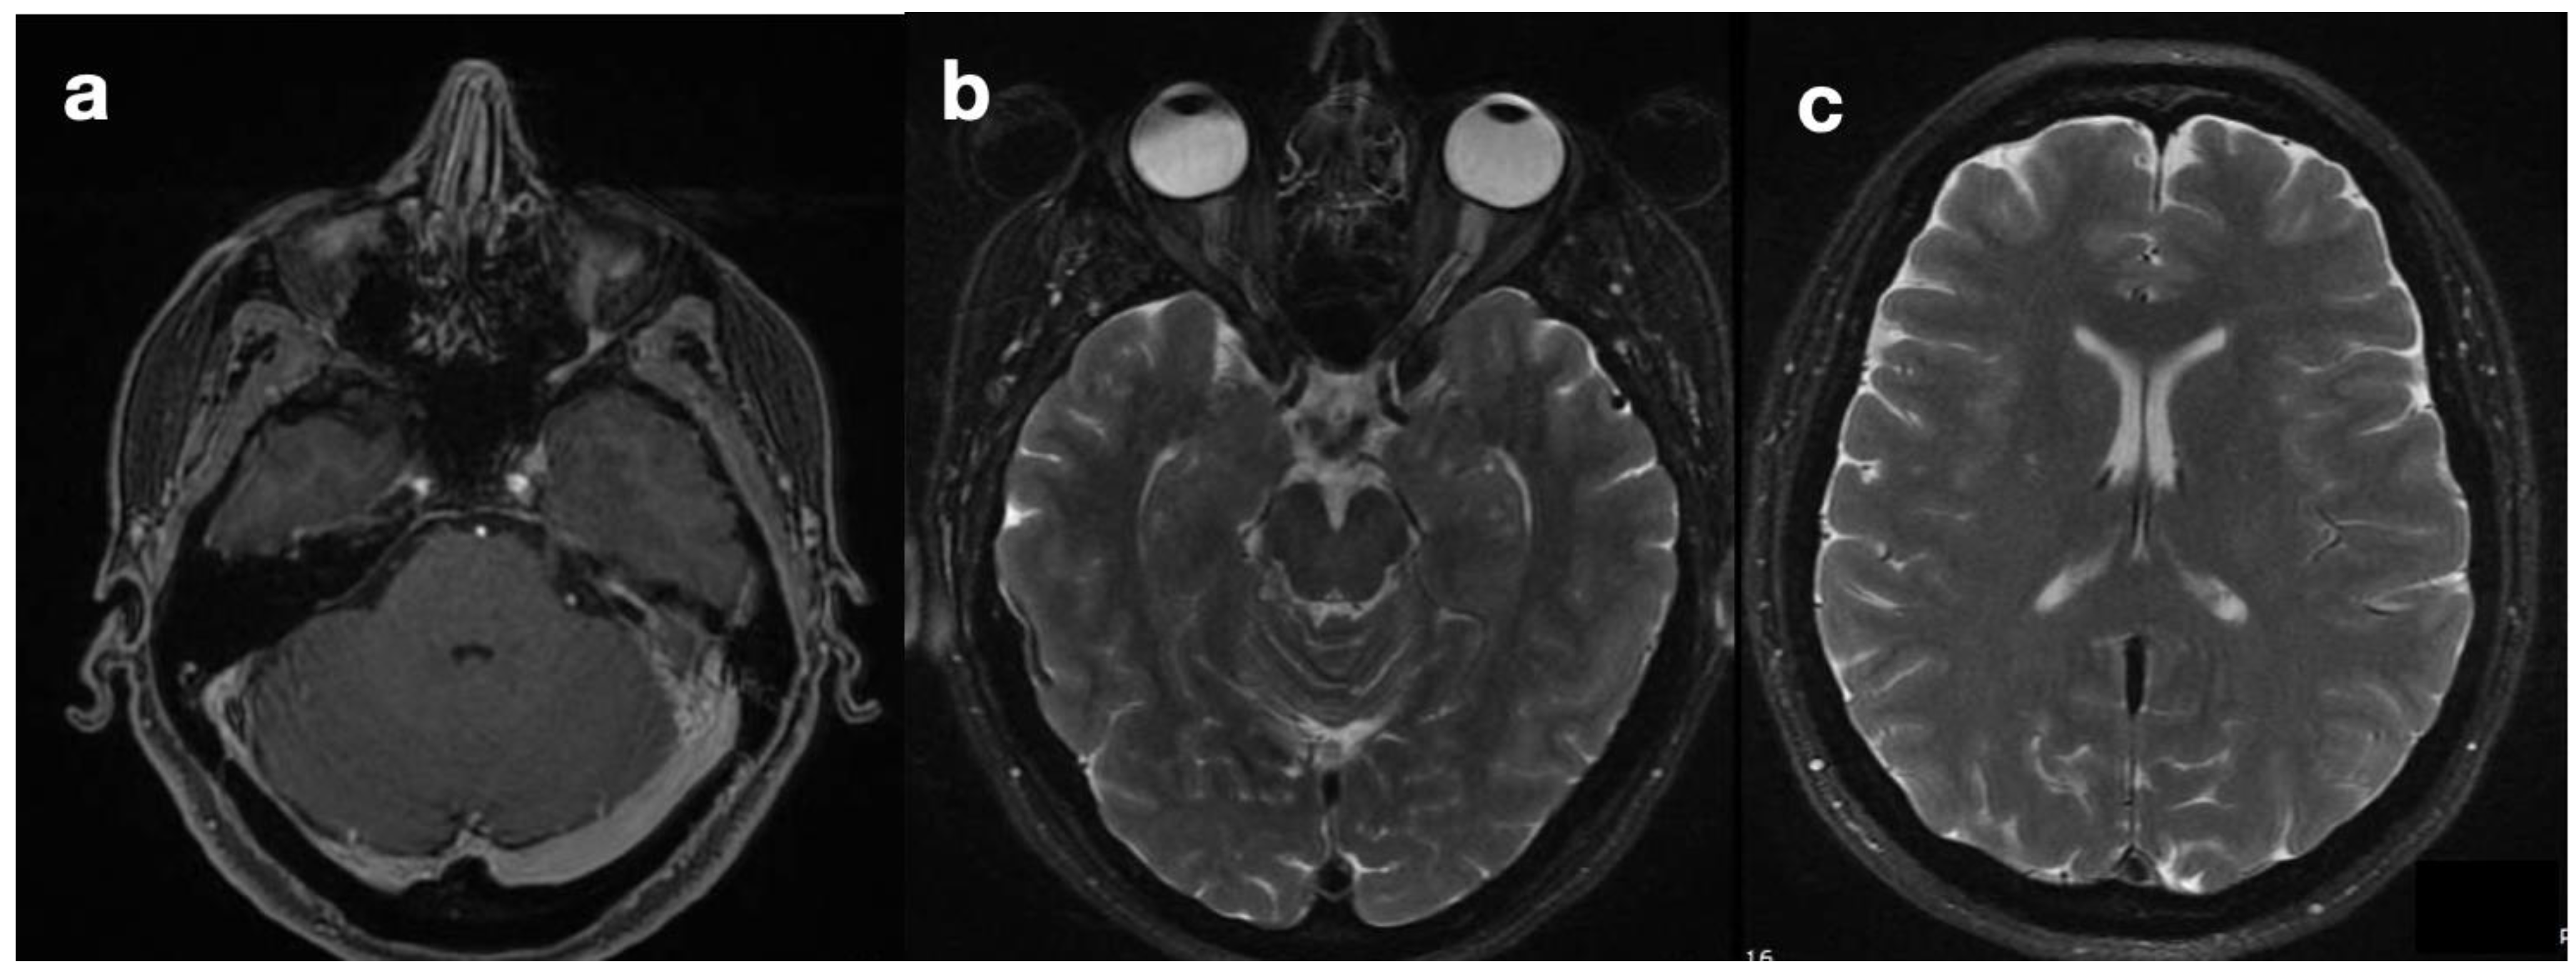

Two years before being referred to our hospital, the patient developed a progressive orthostatic headache combined with mental confusion and lower limb hyposthenia that partially recovered, assuming a supine position. An MR examination revealed isolated dilatation of the fourth ventricle and supposing intracranial hypertension related to IV ventricle hydrocephalus; further ventricular shunting was proposed.

Upon her admission to our hospital, an MRI exam was repeated with contrast media administration. On T2WI, the fourth ventricle was markedly enlarged (Figure 3a and Figure 4a), compressing the pons anteriorly and the cerebellum posteriorly. Accordingly, subtentorial cisterns were effaced. A thin diaphragm was appreciable within the acqueductus Silyii. Axial scans of the enlarged fourth ventricle showed patent and enlarged foramina of Luschka (Figure 3a). T2W hyperintensities in the ventricle walls and around the cranial portion of the central canal suggested trans-ependymal reabsorption and incipient hydromyelia (Figure 4b,c). The MRI exam showed caudal dislocation of the bulbo-medullary junction and herniation of cerebellar tonsils through the foramen magnum. On the other hand, T1W C+ scans showed a diffuse enhancement of the thickened dura mater, surrounded by hyperintense epidural spaces (Figure 4b).

The patient was then diagnosed with isolated dilatation of the fourth ventricle, caused by overdrainage from the SPS causing downward tonsillar displacement as the origin of IV ventricle intracranial and spinal hydrocephalus. The increase in the SPS valve-opening pressure, with subsequent downregulation of the shunt, led to prompt symptom regression and the disappearance of hydromyelia and other MRI signs of trans-ependymal reabsorption (Figure 4e,f).

Isolated dilatation of the fourth ventricle is a rare complication of ventriculoperitoneal shunt surgery, with it being most frequent among pediatric patients and poorly characterized in adults [16,17]. Necessary conditions are, typically, obstruction of the foramina of Luschka and Magendie, inferiorly, and the aqueduct of Sylvius, superiorly. In our case, congenital aqueductal stenosis was present (Figure 4a,d), but foramina were apparently patent—even symmetrically dilated (Figure 3a), while the site of obstruction was farther below. SPS overdrainage caused brainstem and tonsillar sagging, foramen magnum obstruction, and CSF flow trapping in the posterior fossa. Thus, the central canal became the only outflow route available, communicating with the high-pressure closed compartment of the fourth ventricle. Below the foramen magnum, a radial pressure gradient was present from the central canal (abnormally increased pressure) to the spinal subarachnoid space (abnormally decreased pressure). Conspicuous trans-ependymal reabsorption was then provoked in the spinal cord (Figure 4c), at risk of further extension with involvement of the brainstem. The therapeutic approach consisted of only modifying the drainage pressure of the shunt, thus increasing peri-medullary space pressure to normal levels and removing the CSF trapping in the posterior fossa. In turn, this reduced the pressure in the fourth ventricle and removed the gradient established between the central canal and the medullary sub-arachnoid space. The patient’s symptoms rapidly alleviated, without more invasive interventions being required. In subsequent MR examinations, further ascent of cerebellar tonsils was observed, with further resolution of fourth ventricle isolation. Nevertheless, long-term follow-up is needed to monitor the occurrence of late complications, including relapse of overdrainage with spinal subarachnoid space compartmentalization.

Figure 4. Effect of SPD revision on imaging findings. Isolated dilatation of the fourth ventricle is visible before (a) and after drainage downregulation (d). Partial re-expansion of subtentorial cisternal spaces can be seen. A subtle membrane is responsible for the obstruction of the cerebral aqueduct. Signs of peri-ventricular trans-ependymal reabsorption (b) and hydromyelia (c) disappear after shunt revision ((e,f), respectively).